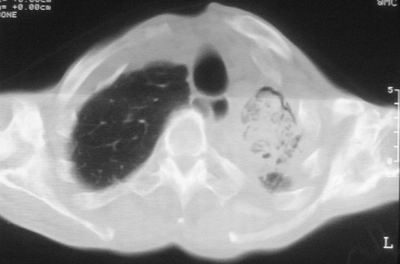

患者,男,47岁,反复咳嗽、咯痰、咯血3年,再发5天。痰培养未找到真菌、抗酸杆菌、癌细胞。

左肺上叶结核伴肺纤维化,纵隔移位,左肺下叶感染性病变,建议抗炎抗结核后复查,双肺气肿.

以下是引用xulianj在2008-2-25 21:01:00的发言:[br]左肺上叶结核伴肺纤维化有霉菌球形成,纵隔移位,左肺下叶感染性病变,建议抗炎抗结核后复查,双肺气肿.

考虑:左肺慢纤伴霉菌球形成、双肺全小叶型肺气肿。

1)考虑为:左肺上叶肺结核(空洞形成),伴左下肺感染;不排除霉菌感染可能。2)肺气肿。

左肺上叶结核伴肺纤维化空洞形成并左肺下叶感染,纵隔牵拉移位,建议作进一步检查排除左侧肺霉菌感染可能。